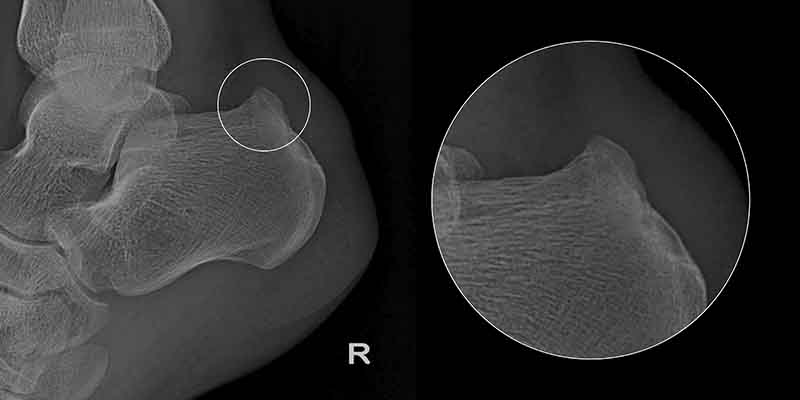

Haglund's disease was first described in 1927 by Patrick Haglund. This condition was initially classified as idiopathic, meaning it has no clear cause, although medical professionals have linked it to several factors. Haglund’s deformity, or "Haglund’s heel," is a condition where an extra bony growth forms on the calcaneus (heel bone), causing irritation and inflammation. This is well illustrated by the X-ray image of a patient’s heel before surgery. Just as people have different nose shapes and sizes, variations in the size and shape of these bones also occur. The protruding bony growth can rub against the Achilles tendon above it, leading to tendon pain. In this case, heel pain at the back is not the result of a single injury but is often related to physical activity and strenuous training (especially running or sports like soccer). However, this is not always the rule, as heel pain can also affect individuals with no connection to sports.

The first symptom is pain at the back of the heel, over the bony prominence, without significant swelling. Early symptoms are mild, leading only to discomfort while walking. Patients report pressure in the rear part of the heel, especially when putting on shoes. Initially, the symptoms are not severe or bothersome enough to prompt a visit to the doctor. This allows the deformity of the heel bone to progress over time. Gradually, these symptoms worsen, leading to noticeable limping while walking. Heel pain most often occurs after physical activity or in the morning but rarely at night. Over time, the heel develops a visible deformity accompanied by painful swelling, as shown in the images. In such an advanced stage of the condition, the calcaneus becomes very painful, especially during dorsiflexion of the foot. A further stage may involve inflammation at the Achilles tendon attachment to the calcaneus.

Haglund’s deformity can often be diagnosed through a physical examination, but X-rays are necessary to confirm the diagnosis and rule out other causes of heel pain, such as assessing the structure of the calcaneus. With an early diagnosis and the initiation of conservative treatment, Haglund’s deformity offers good prognoses for patients. Non-surgical treatment focuses on reducing inflammation of the bursa and begins with rest and significantly reducing physical activity. To decrease swelling, ice packs should be applied to the inflamed area (cooling the heel for 20 minutes, followed by at least a 40-minute break before repeating). Doctors may prescribe oral non-steroidal anti-inflammatory drugs (e.g., ibuprofen) to alleviate pain and inflammation.